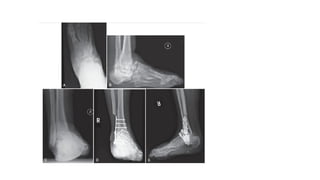

A and B, End-stage ankle arthritis. C and D, After mini-incision ankle arthrodesis;

use of “home run” screw from posterolateral tibial into talar neck/head distally